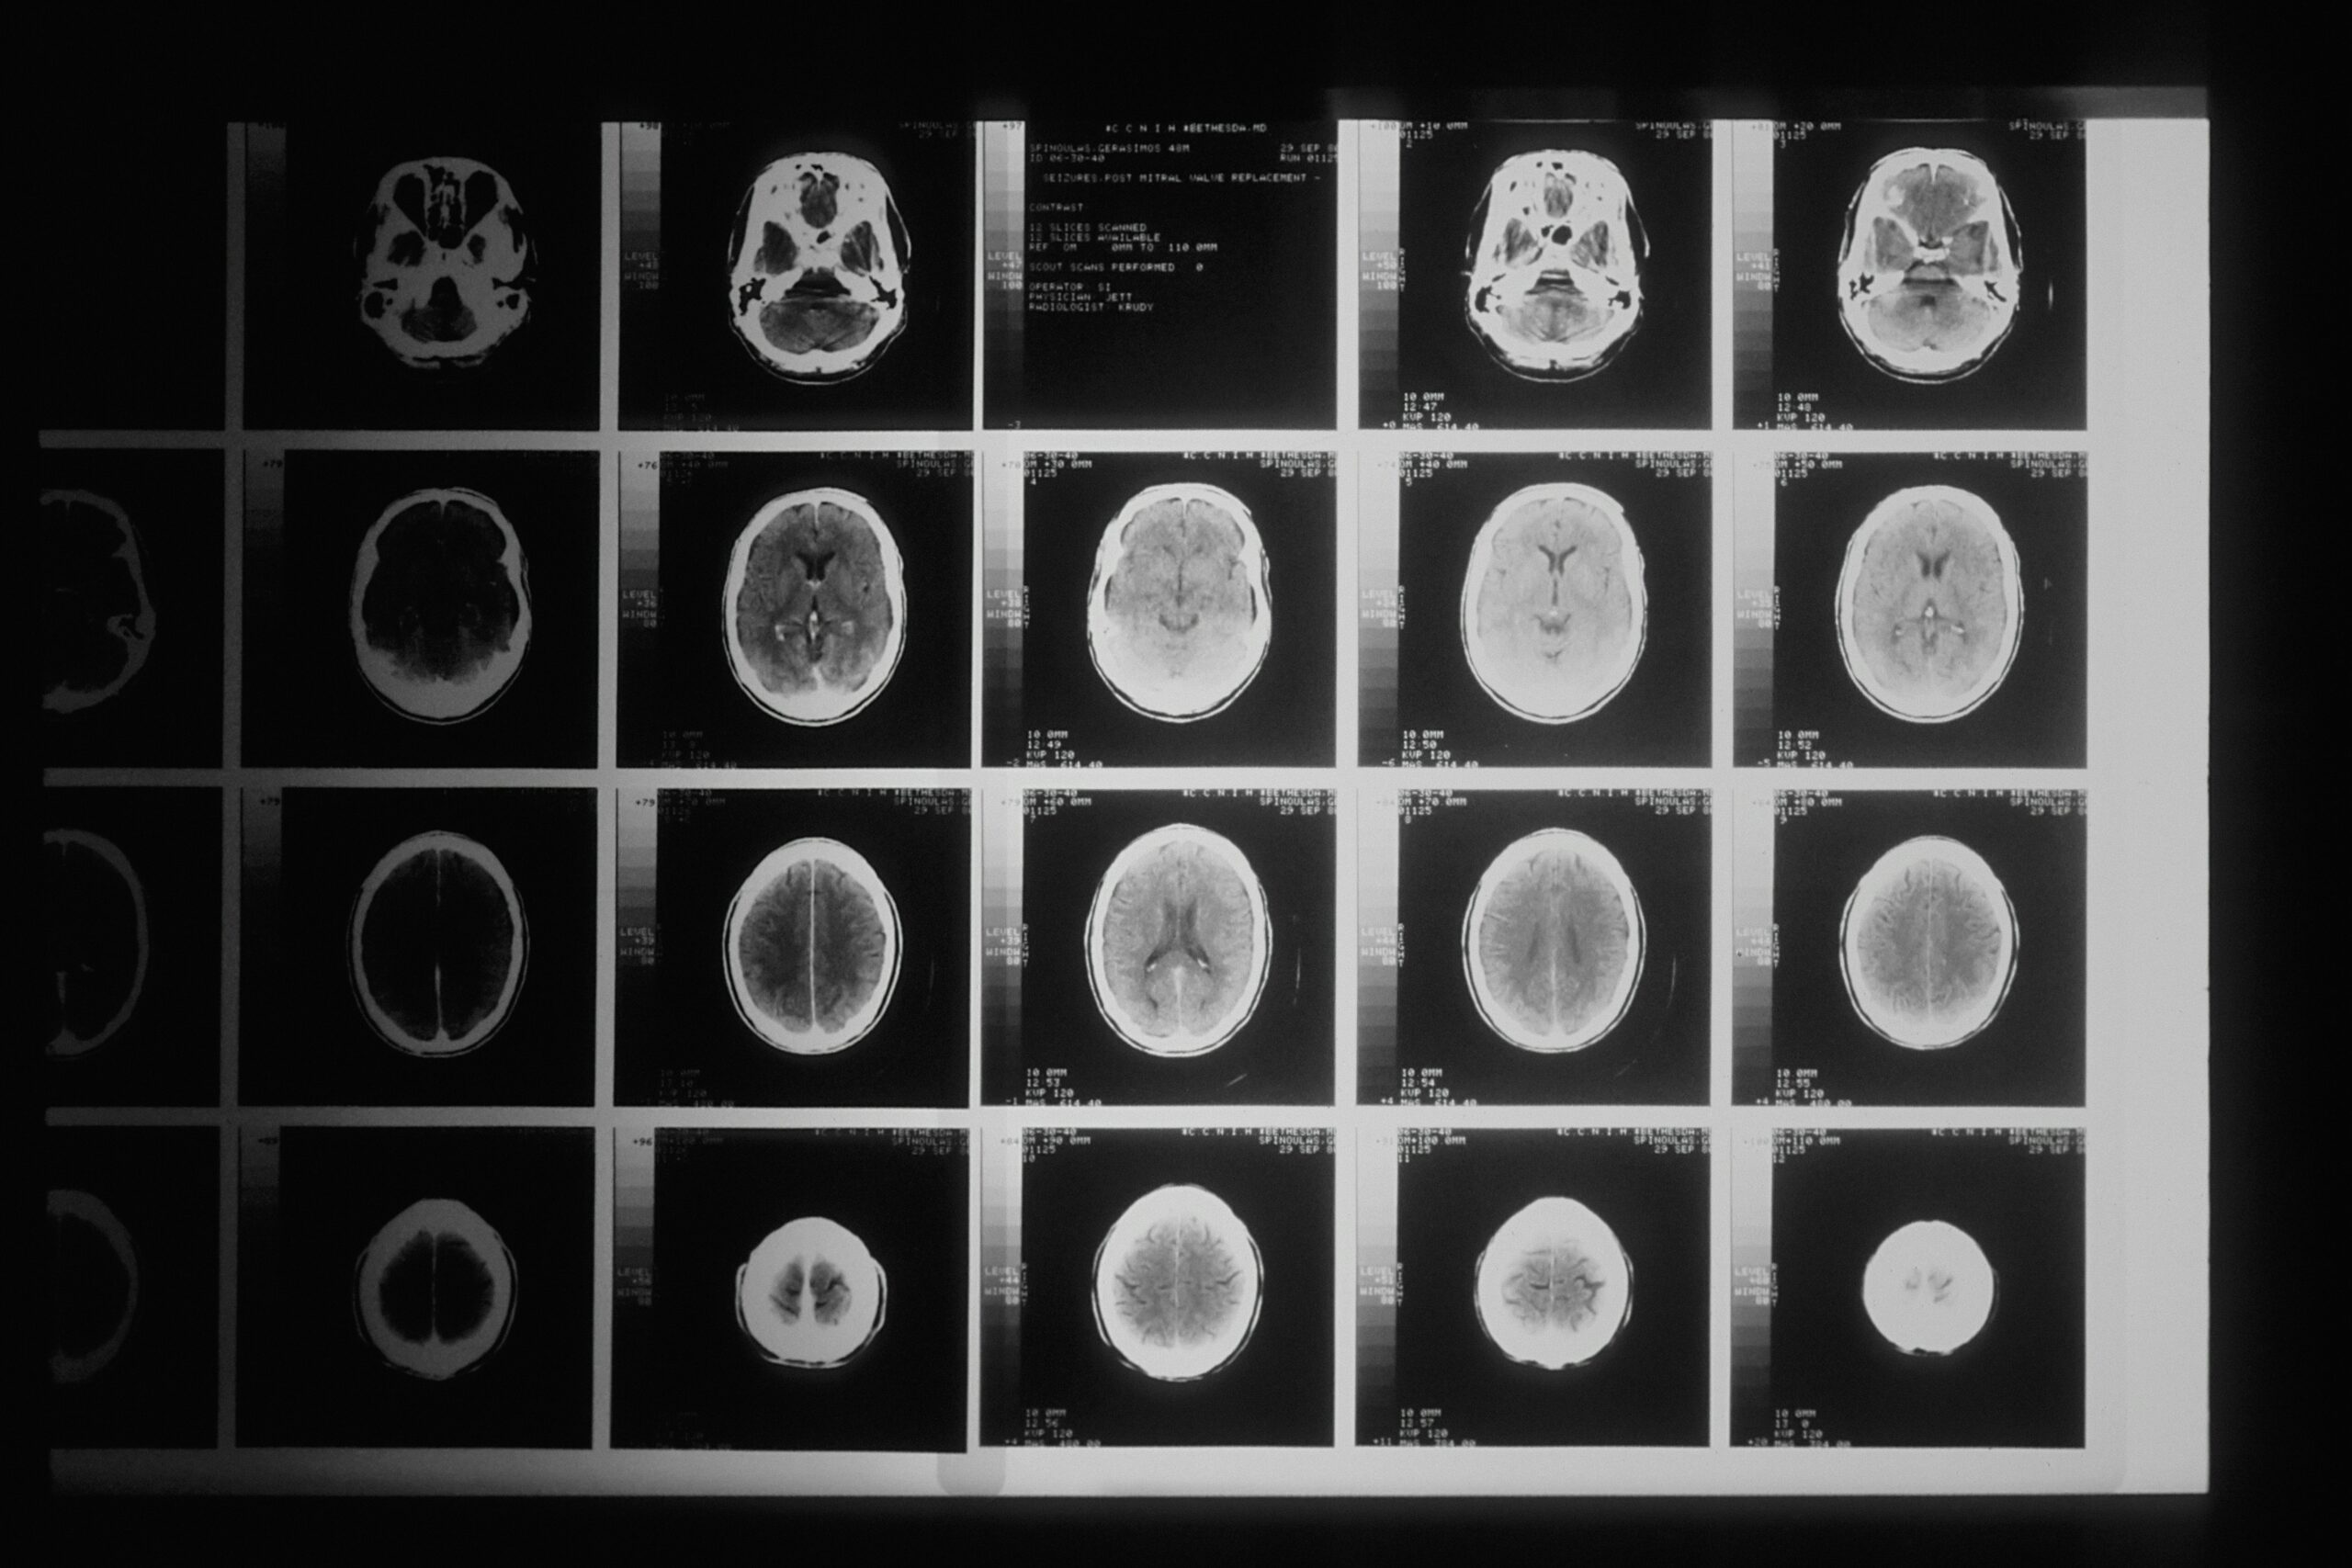

Privacy-preserved Syntheic Data in Healthcare

The Role of Data in Healthcare Organizations

Data usage in healthcare organizations is crucial for enabling evidence-based medical decisions, personalized treatments, and medical research. This leads to enhanced patient outcomes, improved operational efficiency, and advancements in medical knowledge and technologies. Synthetic data offers a privacy-preserving alternative by creating realistic and non-sensitive datasets, empowering researchers, clinicians, and data scientists to innovate, validate algorithms, and conduct analyses without compromising patient privacy.

AI Healthcare Market Value by 2027: $67.4 billion

Insufficient Access to Patient Data: 60% of consumers.

Health Records as Targets: 95% of identity theft cases.

AI in Healthcare IT by 2024: 60% adoption for automation and decision-making.